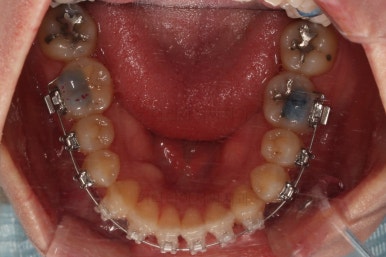

초진 시, 입안의 모습입니다.

좌측 송곳니가 덧니처럼 튀어나가 있고, 송곳니 옆의 작은 억므니가 안으로 쏙 들어가서 덧니 느낌이 더 강조되어 보이네요.

위아래 앞니가 긴밀하게 겹침이 없는 약간의 개방교합(오픈바이트, Openbite) 경향이 보입니다.

이번에 선택하신 장치는 자가결찰 세라믹 중에 엠파워 클리어라는 장치인데요.

흔히들 아시는 클리피씨도 같은 분류의 장치입니다.

철사가 들어가니 삐뚤한 치열이 더 강조되어 보이네요.